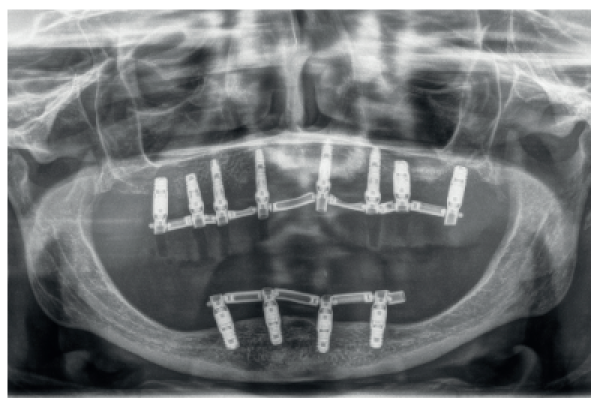

4 | CASO CLÍNICO | ATROFIA COMBINADA MAXILO-MANDIBULAR. USO DE IMPLANTES CORTOS Y ESTRECHOS (BTI® CORE Y BTI® 3.0) |